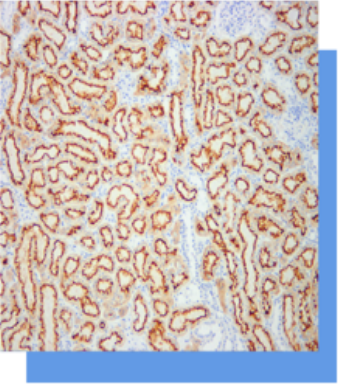

Villin(微管素)抗体试剂

Villin是一种分子量为95kDa的细胞骨架蛋白,正常分布

于肠.上皮和肾近曲小管上皮,可用于肠上皮来源肿瘤与

非肠上皮肿瘤的肿瘤的鉴别判断,亦可作为胃肠道神经

内分泌肿瘤诊断的参考指标。